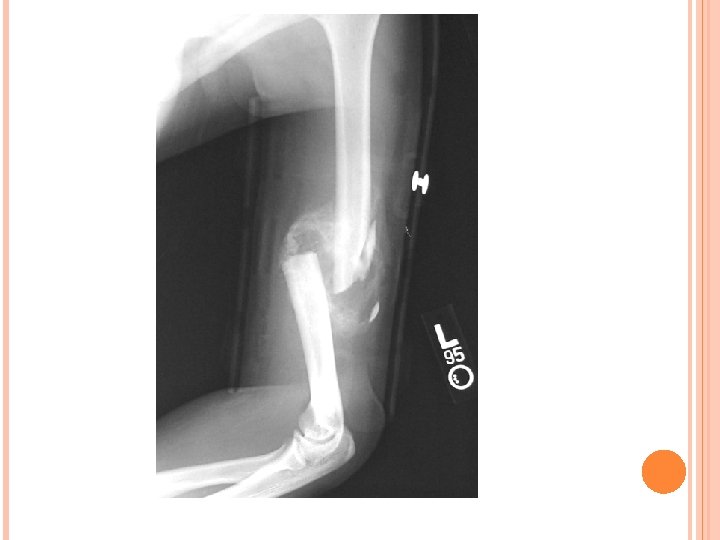

Humeral Fractures- May be hard to detect because of musculature unable to move arm and experiencing pain, most likely felt or heard a pop Splint, and check distal pulse

BONE INJURIES CONT… Epiphysis Growth Injury plate in young athlete Direct or indirect blow Mimic humeral fx- pain, inability to use arm, guarding, feeling/hearing pop Can cause permanent growth impairment Rehab- ice, splint, and refer to physician

BONE INJURIES CONT… Avulsion Tearing Fracture bone off with ligament May accompany a AC or GH sprain P! associated with fx Almost IMPOSSIBLE to detect unless r/o by x-ray Splint and ice, refer to MD

GH Dislocations and Subluxations X-ray is necessary to determine extent of injury Permanent changes to the nerves, cartilage, and blood vessels Rehab: strengthen muscles of adduction and internal rotation, restrict abduction and external rotation, Harness and Surgery is likely

4. Dislocation to the Glenohumeral Joint: Anterior displacement of the humerus is caused by forced abduction and external rotation. Dislocation can tear the capsule, ligaments and labrum. Displays a flattened deltoid and severe pain and disability. Injury is beyond the scope of an athletic trainer’s duties, athlete needs a referral for x-rays and reduction.